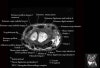

- Axial section

Axial T1 evaluates the tendons of the wrist and carpal tunnel, including the flexor retinaculum.